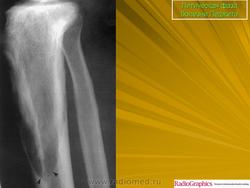

Литическая фаза.

Принято различать три фазы развития П. б.: очаговая интенсивная резорбция кости (остеолитическая, или деструктивная, фаза), смешанная фаза, когда наряду с рассасыванием кости идут процессы новообразования ее, и остеобластическая, или склеротическая, фаза с образованием типичных мозаичных структур.